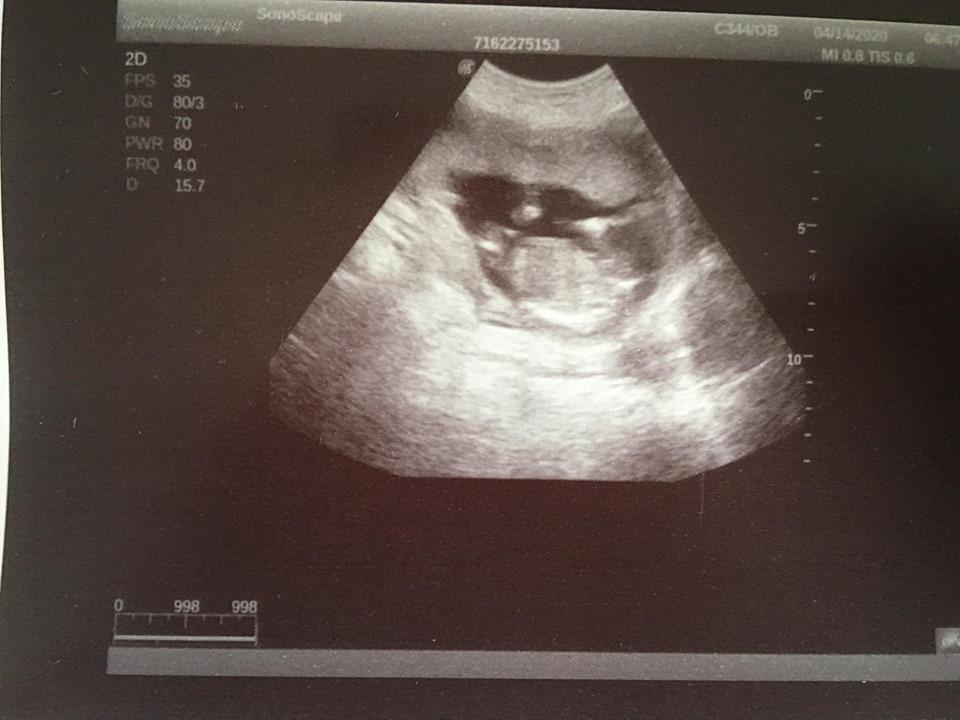

Je to holčička nebo chlapeček? Foto ultrazvuku

@lilian2111 já se v těch hrbolcích vůbec,ale vůbec nevyznám hah 😀 😀 ale pamatuji si u kluků,že ten pinďour šel vidět jasněji na těch prvních screeningách než teď u malého Damiánka či Dominička 😀 😀

@juliemichal škoda, že ta fotka je rozmazana. Ale vypadá to spíš na kluka, opravdu tam něco trčí, ale na tento týden by to byl tedy už poradny chlapak 😃 až půjdete v tom 15+4, poproste o fotku pohlaví ze spodu, to už by mělo být pohlaví poznat.

@kajda3 no to je fakt na 12+1 by to byl pořádný chlapák hah,takže to co tam trčí to určitě nebude šula 😀 😀 ale uvidíme ♥ ♥ určitě v úterý poprosím dr aby mi dala fotečku pohlaví ♥ ♥

@sebinka123 kéž by ta první fotka (screening) podle dr to vypadá na kluka,druhá fotka 2 dny později u mého gynekologa ten mi řekl,že mezi nožičky nic nevidí,že by ho zajímalo kde doktor viděl chlapečka 😀 😀 ale,že z největší pravděpodobností mi pohlaví řekne až ve 20tt

@juliemichal to jsem na tebe zvedava! 😁 musíš nám dat v úterý hnedka vědět. První fotka bych řekla na 99% kluk, ale ta druha zase vypadá na holčičku. Moc bych ti tu holčičku prala 🙂

jinak koukej první foto 14+5 tj dnes,druhé foto 14+1 třetí těhotenství s Mateem 😀 😀 a mám ty břicha úplně jiné u kluků jsem měla úplně stejné jako u Matea a teď fakt úplně jiné 😀 😀

@eiram7 jasná holčička, gratuluji 💃ve 13. týdnu je to jisté tak na 95 % 😊 navíc k tomu tento snímek hrbolek ukazuje pěkně 👍